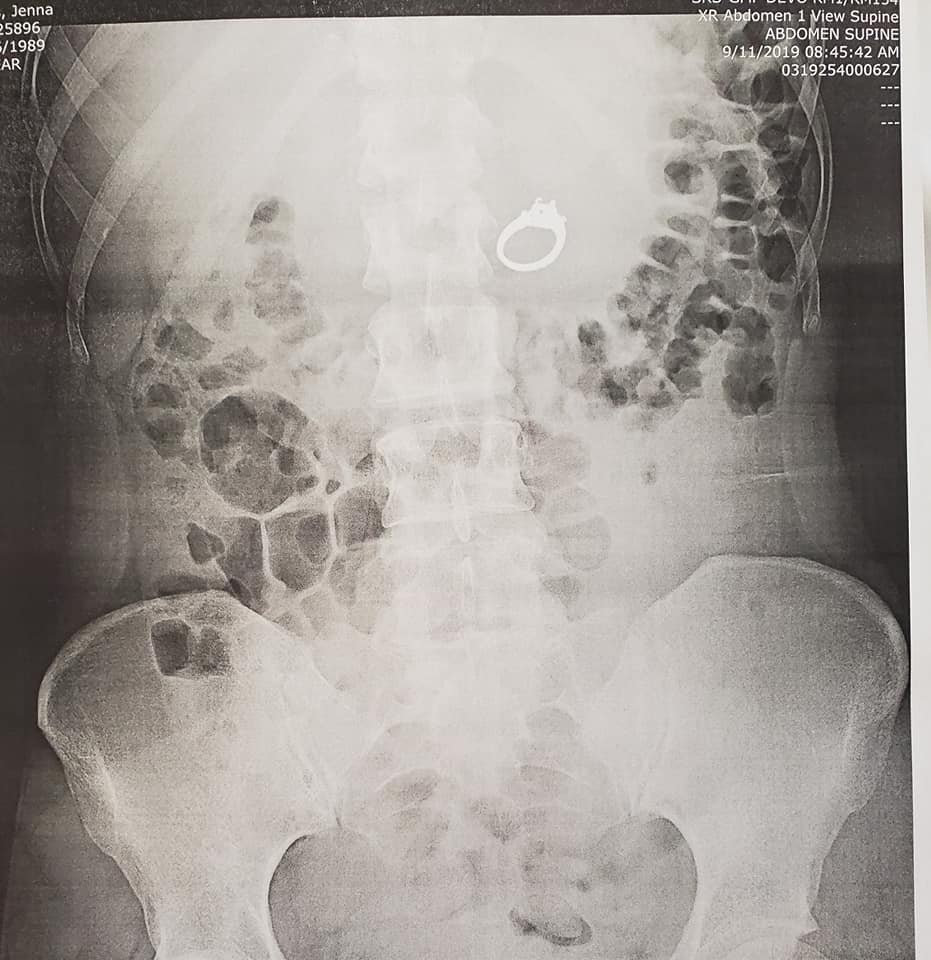

Primero ubicaron el anillo de compromiso a través de Rayos X y después la sometieron a una cirugía. A pesar de que el procedimiento quirúrgico fue un éxito, Evans comentó que despertó llorando histéricamente por los efectos de la anestesia.